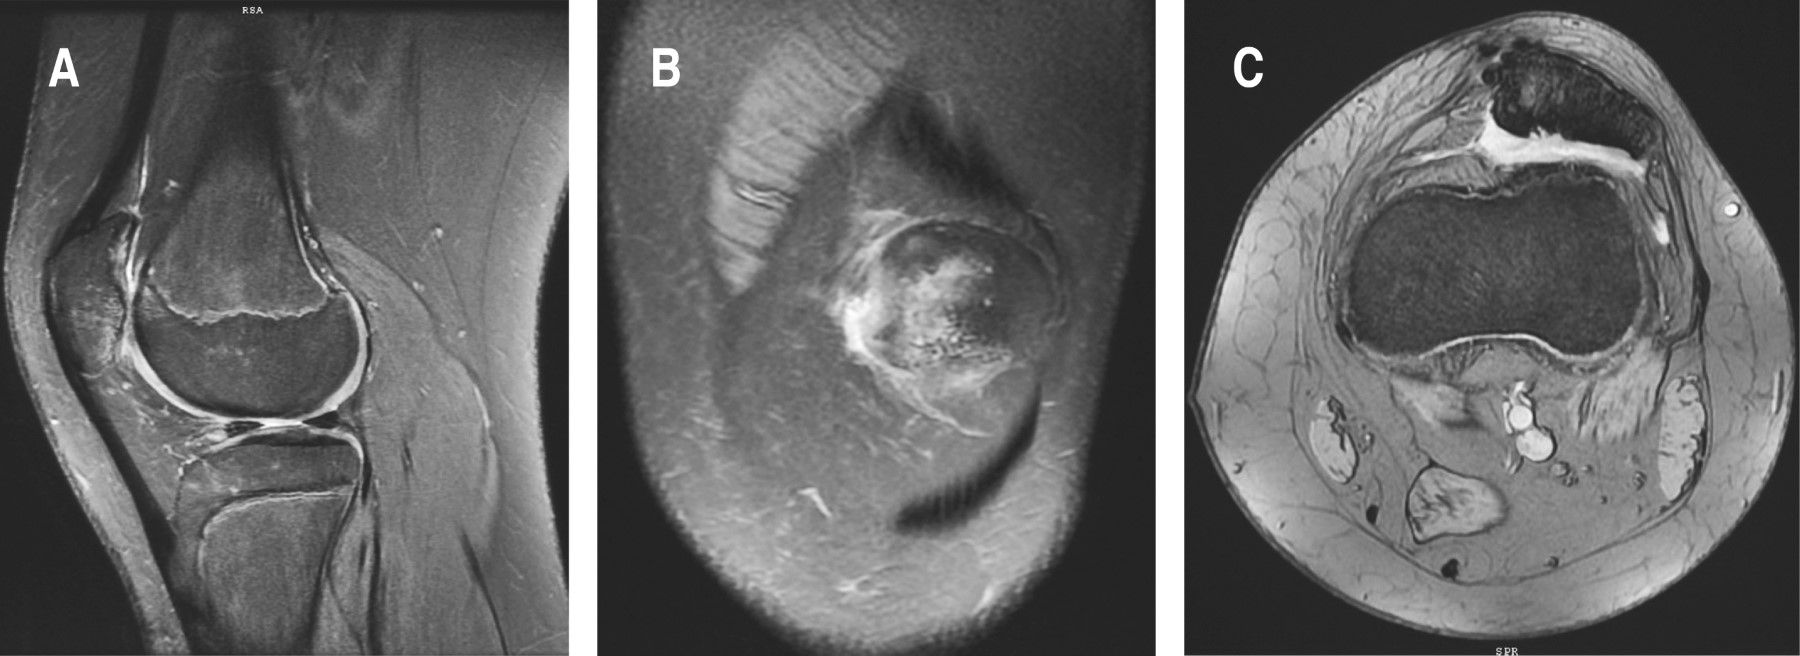

A los 24 meses se le realizó una resonancia magnética de control de la rodilla afectada. En todos los cortes se observaron áreas de consolidación ósea, que mostraron una adecuada reparación del trazo de fractura (Figura 6).

Figura 6